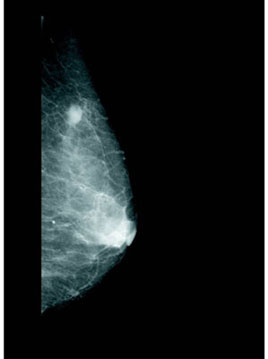

乳腺X線攝影是一種備受關注的X線攝影技術,因為乳腺疾病(如惡性腫瘤)在圖像上的顯示十分微小,并且病變形狀也非常重要。

醫生不僅要仔細檢查圖像上方的白色塊狀陰影(圖6),還要查究直徑僅為幾百微米的白色微斑(微小鈣化),并且要注意它們的形狀。這種微小鈣化極為重要,被認為是乳腺癌(原發性乳腺癌)的征兆。

柯尼卡美能達公司希望推動乳腺X線攝影的數字化,通過應用顯著提高圖像清晰度的相位對比技術提供前所未有的高品質圖像,從而為根治日益增多的乳腺癌患者做出貢獻。

圖6 乳腺X線攝影